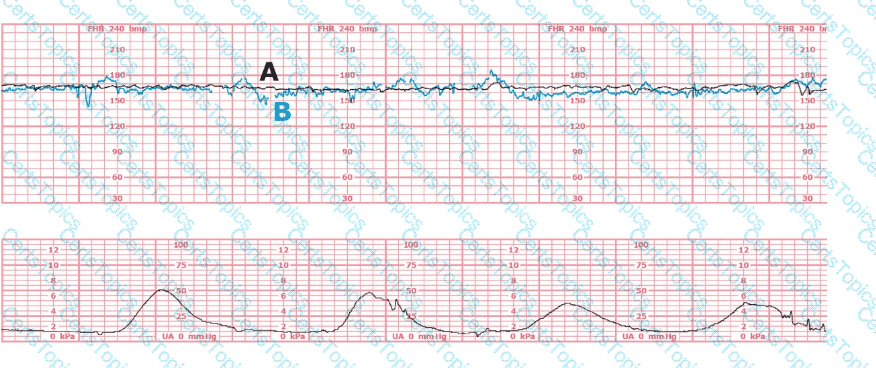

This fetal heart rate tracing is of a woman in labor with dichorionic-diamniotic twins at 36-weeks gestation, 4 cm dilated. She is on oxygen via face mask. Based on the fetal heart rate tracing, what is the most appropriate action?

(Tracing A = black; Tracing B = blue)

The black pattern represents the heart rate pattern for Baby A. The blue pattern represents the heart rate pattern for Baby B. A possible etiology of the baseline fetal heart rate of Baby A is: